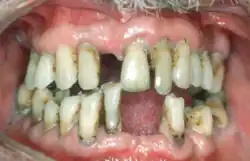

Periodontal disease, also known as gum disease, is a set of inflammatory conditions affecting the tissues surrounding the teeth.[5] In its early stage, called gingivitis, the gums become swollen and red and may bleed.[5] It is considered the main cause of tooth loss for adults worldwide.[7][8] In its more serious form, called periodontitis, the gums can pull away from the tooth, bone can be lost, and the teeth may loosen or fall out.[5] Halitosis (bad breath) may also occur.[1]

| Symptoms | Red, swollen, painful, bleeding gums, loose teeth, bad breath[1] |